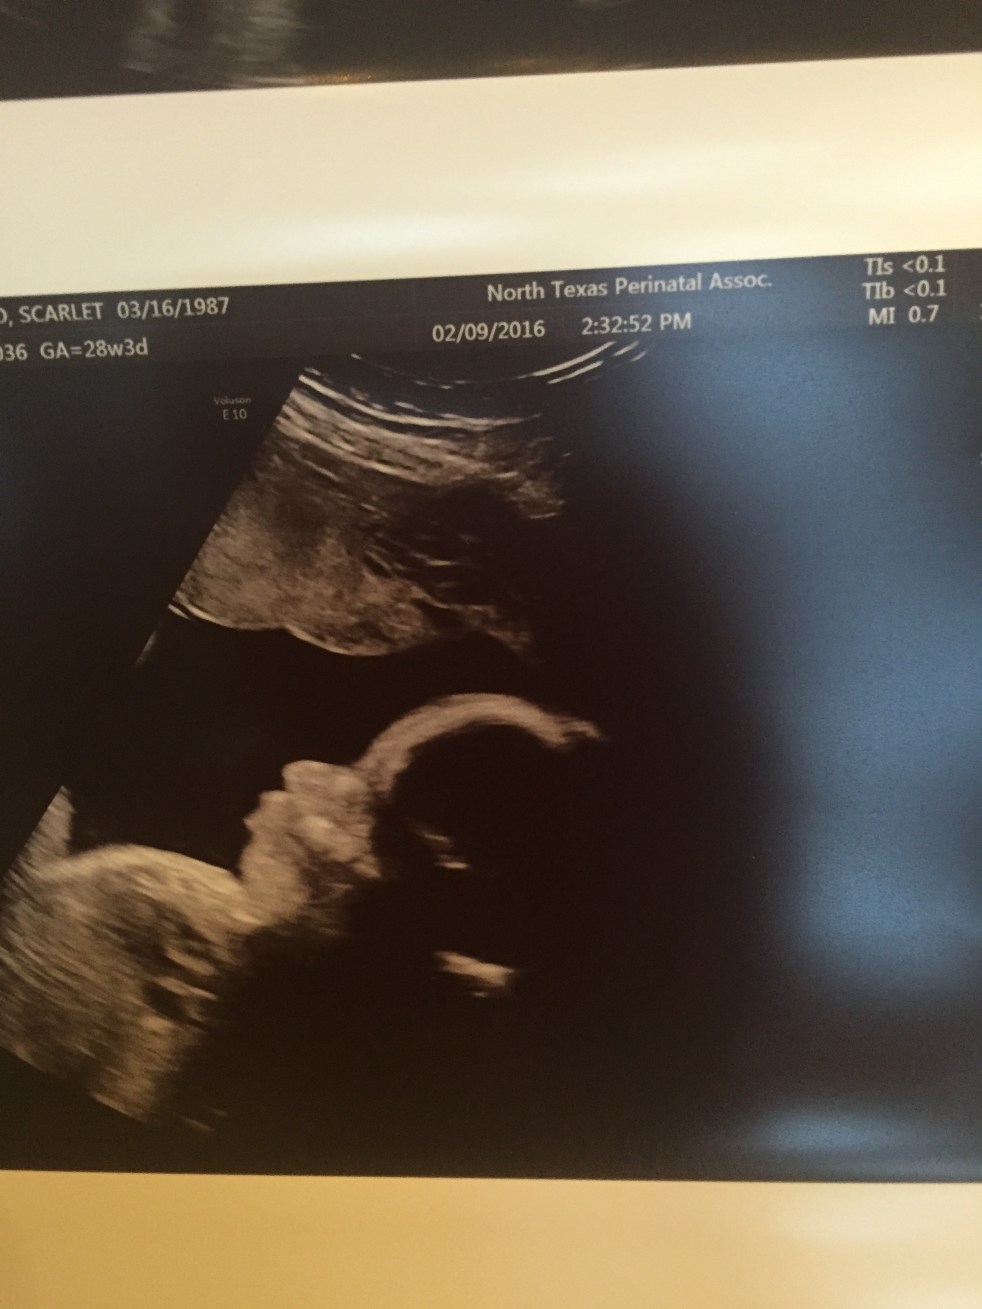

18 Week Update: This is fun?

This is fun. This is fun. This is fuuun?? That is what I keep trying to tell myself. Pregnancy is supposed to be fun. Exciting. Thrilling. Beautiful. Well, pregnancy after loss is not so fun. Don’t get me wrong, I am not complaining about being pregnant. I am complaining about the feelings that come with being pregnant… Continue reading 18 Week Update: This is fun?